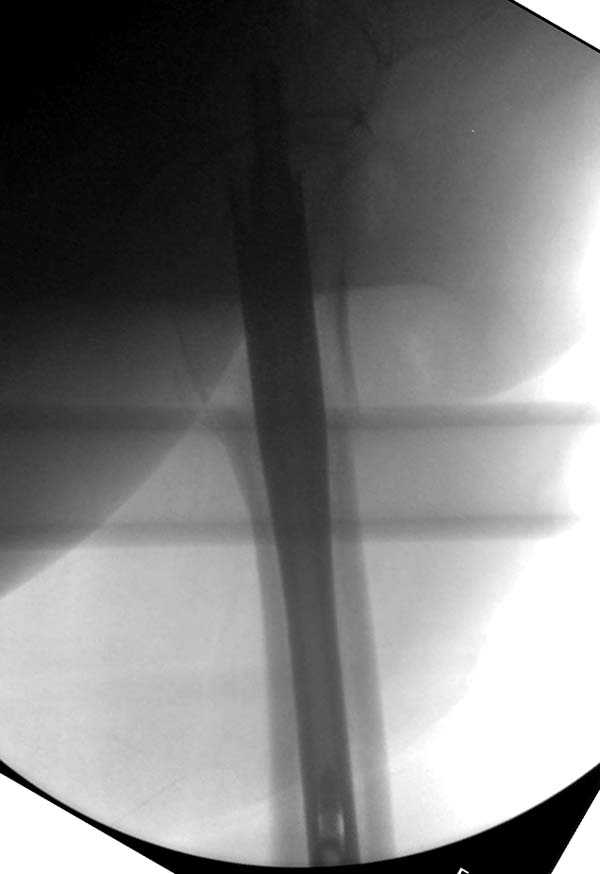

При первом послеоперационном поликлиническом осмотре больная предъявила жалобы на боли в бедре. В серийных снимках обнаружен продольный перелом верхнего отдела бедра.

Считаем, что техническая ошибка произошла во время установки гвоздя, когда рассверливанию канала не уделили должного внимания. Канал остался узковат, и гвоздь был забит с силой. Полная нагрузка конечности приостановлена на две недели, и боли в конечности изчезли. Больная начала нагрузку и перелом срастается.-- Djoldas Kuldjanov, M.D.Associate ProfessorDepartment of Orthopedic SurgerySt. Louis University

Мне думается, что варусное положение проксимального отломка на последующих снимках не более чем проекционный феномен. Раскол же диафиза вдоль, наверняка, связан с чрезмерно насильственным введением штифта. Вообще, при реверсивных, да и обычных вертельных переломах, многие давно отказались от короткой Гаммы в пользу long-версии. Но в любом случае надо быть на 100 уверенным в подготовке канала.